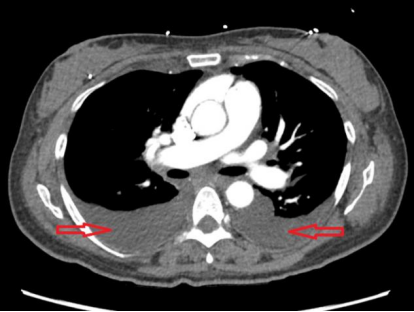

(1) 下肢B超:检查结果排除深静脉血栓形成(2)心电图:显示为窦性心律,存在 R 波递增不良(QTc 485ms)(图1),可排除急性冠脉综合征;(3)胸部 X 线(入院时):可见双侧斑片状阴影及双侧胸腔积液(图2);(4)病原学检查:入院时血培养、尿培养结果均为阴性,且住院期间无感染相关症状与体征,因此双侧斑片状阴影由感染因素导致的可能性较低,更倾向于与急性心力衰竭相关;(5)肺血管 CTA:因患者存在心悸、呼吸急促症状且 D - 二聚体水平轻度升高,遂完善此项检查以排除肺栓塞。结果显示双侧中量胸腔积液、轻度间质性肺水肿及轻度心脏肥大,提示存在充血性心力衰竭(CHF)(图 3、图 4),同时可见散在肺部阴影;(6)经胸超声心动图(TTE):显示左右心室大小正常、收缩功能正常,无局部壁运动异常;左心房大小为 2.93cm(正常范围 1.9-4.0cm),处于正常水平;肺动脉收缩压(PASP)为 34mmHg,存在轻度同心性左心室肥大,心室射血分数为 55%-60%。 (7)核素心肌灌注显像负荷试验:因心电图异常进行此项检查,未发现可逆性缺损,表明无心肌缺血;(8)腹部 / 盆腔 CT:患者肝炎免疫检测结果为阴性,肝转氨酶升高大概率由充血性心力衰竭(CHF)继发的充血性肝淤血引起。为进一步明确情况,行腹部 / 盆腔 CT 检查,显示存在胆结石、胆囊壁增厚 / 水肿、门静脉周围水肿所致的轻度肝肿大,同时伴有新出现的轻度全身性水肿及少量盆腔积液;(9)胸部 X 线(出院时):显示肺充血消退,双侧胸腔积液较入院时减少(图 5)。

图4